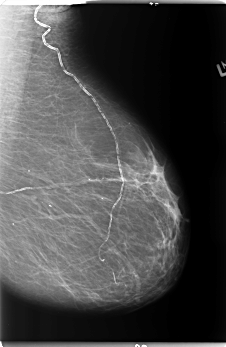

B_3141_1.LEFT_MLO

LEFT_MLO LINES 5888 PIXELS_PER_LINE 3840 BITS_PER_PIXEL 12 RESOLUTION 50 NON_OVERLAY